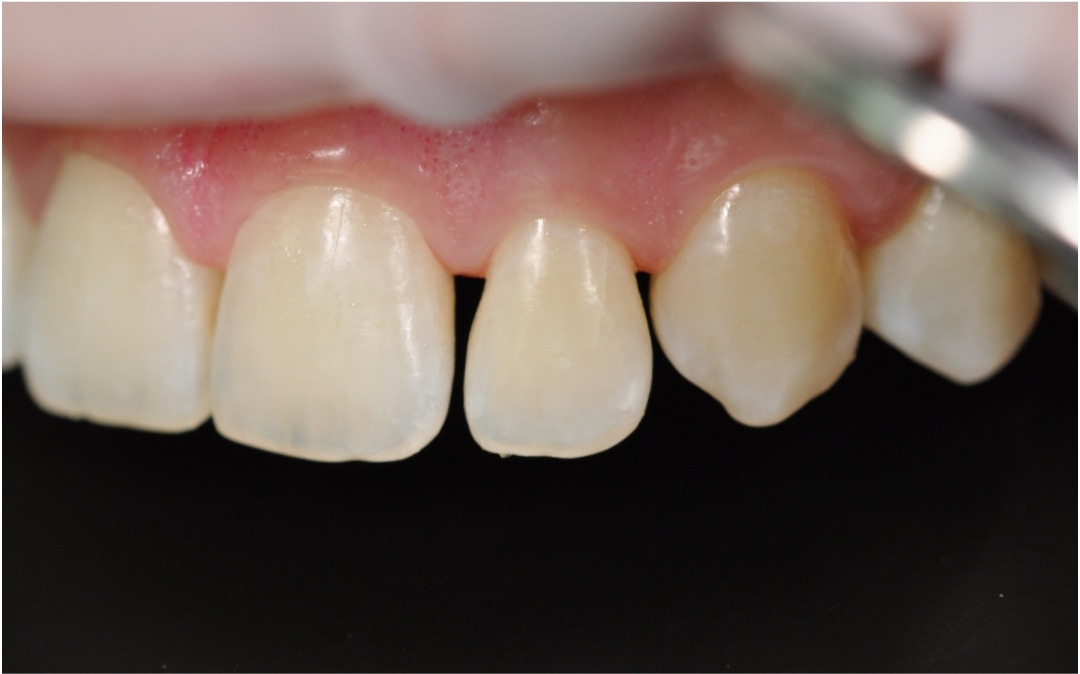

До

Помимо физического дискомфорта, пациентку не устраивала эстетика улыбки. В частности, форма и положение зубов.